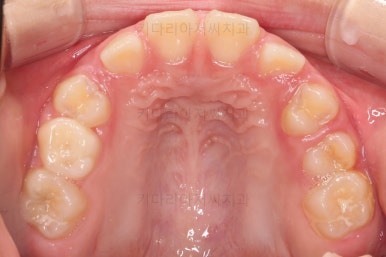

초진 시 입안의 모습입니다.

아래쪽 치열이 전반적으로 윗니보다 앞쪽에 위치한 전형적인 앵글씨 3급 부정교합인데요.

어금니에서부터 앞니까지 아랫니가 윗니보다 앞쪽에 위치하네요.

특히 앞니는 아랫니가 윗니보다 나와있는 "반대교합" 상태였고요.

또한 위아래로 겹침이 없고 떠있는 "개방교합" 상태였어요.

즉, 앵글씨 3급 부정교합 - 반대교합 - 개방교합 등 굉장히 복합적인 교합의 문제를 가진 환자였습니다.